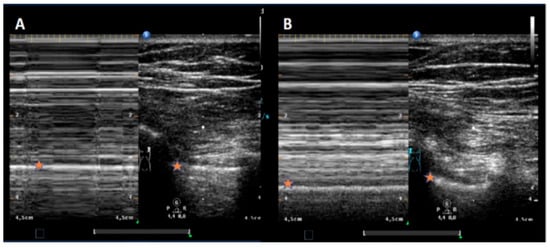

Background: The incidence of iatrogenic pneumothorax (IPTX) following transbronchial lung cryobiopsy (TBLCB) ranges from 1.4% to 20.2%. While chest X-ray (CXR) is the standard imaging modality to exclude IPTX, thoracic ultrasound (TUS) has demonstrat...